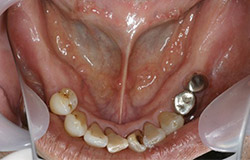

インプラントで噛み合わせの再構成を伴った症例。

治療後のメンテナンスを行わないと

周囲炎になるリスクあり。